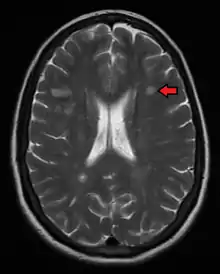

Magnetic resonance imaging (MRI) of the brain and spine may show areas of demyelination (lesions or plaques). Gadolinium can be administered intravenously as a contrast agent to highlight active plaques and, by elimination, demonstrate the existence of historical lesions not associated with symptoms at the moment of the evaluation.[62][63]